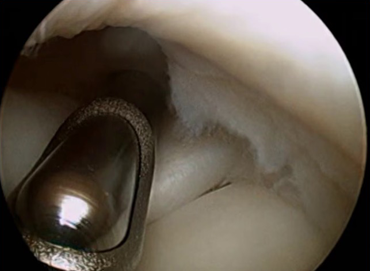

A artroscopia é um método utilizado para realizar procedimentos dentro ou ao redor da articulação do ombro. Existem várias indicações para a artroscopia do ombro, sendo as mais comuns a lesão do manguito rotador (lesão tendinosa) e a instabilidade do ombro (quando o ombro sai do lugar). Embora sejam cirurgias diferentes, ambas utilizam o mesmo método: a artroscopia, que consiste no uso de uma câmera de vídeo e pinças específicas. No caso da correção da lesão do manguito rotador, muitas vezes é necessário remover (raspar) um esporão ósseo antes de realizar a sutura do tendão rompido no seu devido lugar. Vale lembrar que existem diversos tipos de lesão tendinosa, e cada caso deve ser cuidadosamente avaliado para que se escolha a melhor técnica possível.

A artrose do ombro é o desgaste da articulação que pode ocorrer devido ao uso excessivo, a fatores genéticos (artrose degenerativa) ou como sequela de um trauma prévio. Independentemente da causa, é comum que o paciente apresente diminuição dos movimentos do ombro, dor e crepitação (um barulho percebido ao movimentar a articulação). É fundamental realizar uma avaliação minuciosa tanto da condição da articulação quanto dos tendões do manguito rotador, para que se possa indicar o tratamento mais adequado, já que a doença pode se apresentar em diferentes estágios. O tratamento varia conforme a idade do paciente e o grau de comprometimento da articulação, podendo ir desde abordagens por artroscopia até a necessidade de uma artroplastia (prótese), seja ela parcial ou total.